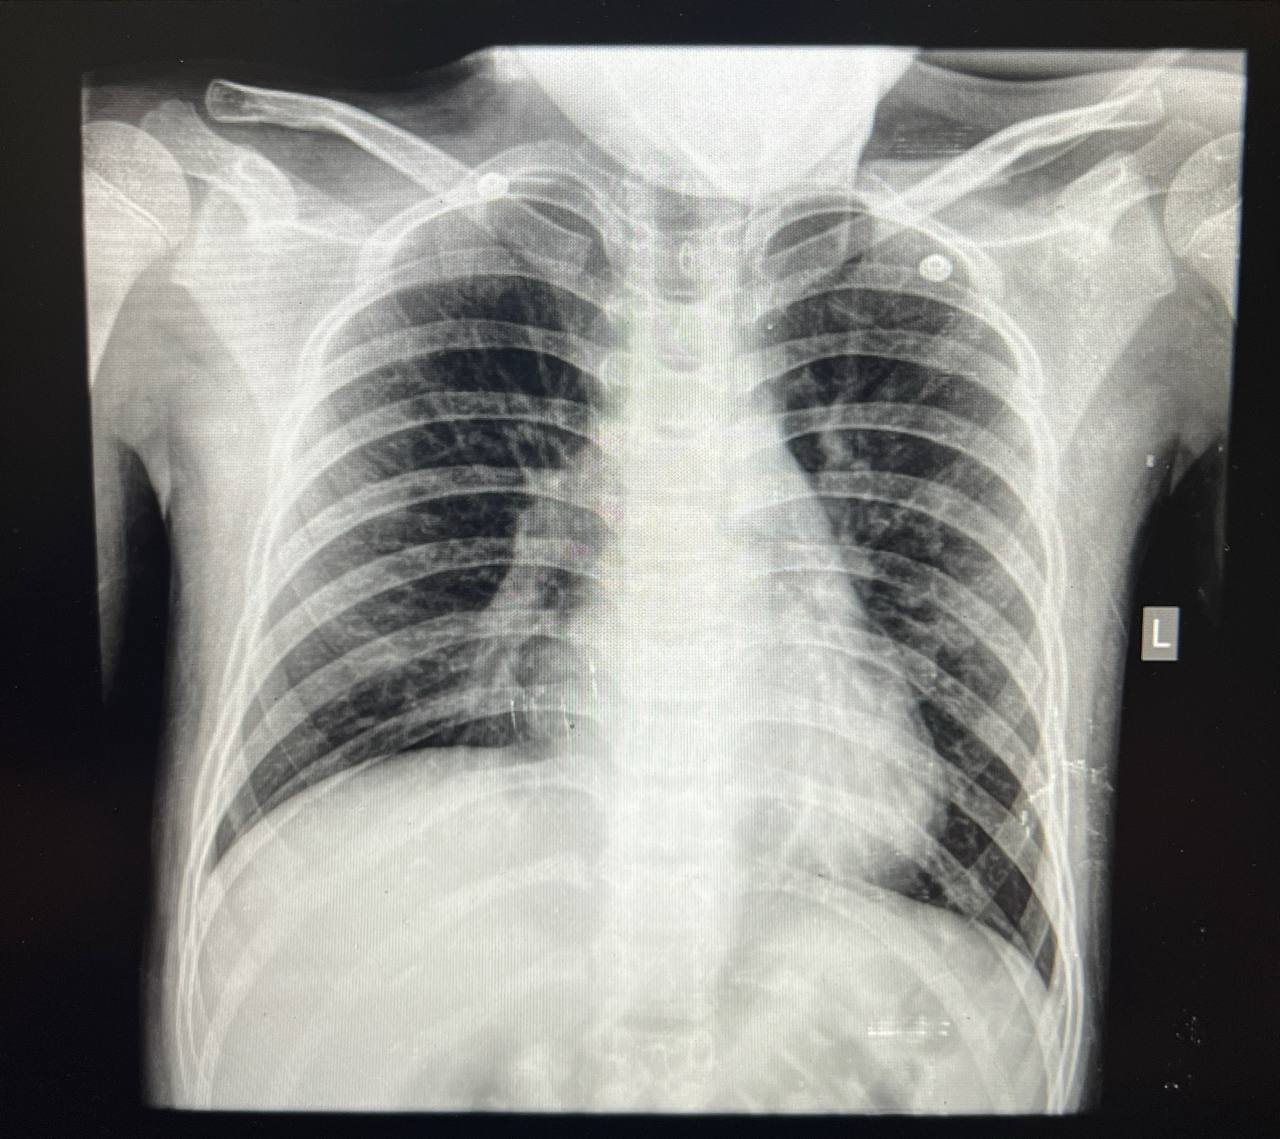

شکم نرم و بدون تندرنس و گاردینگ و ارگانومگالیپنونمونی اتیپیک با توجه cxr

افزایش پترن واسکولار داره با ارجحیت سمت راست ولی دو طرفه، که سمت راست تقریبا به سمت کانسالیدیشن داره پیش میره. چست هم PA هست

عدم نمای پر هوایی=Rule out bronchiolitis